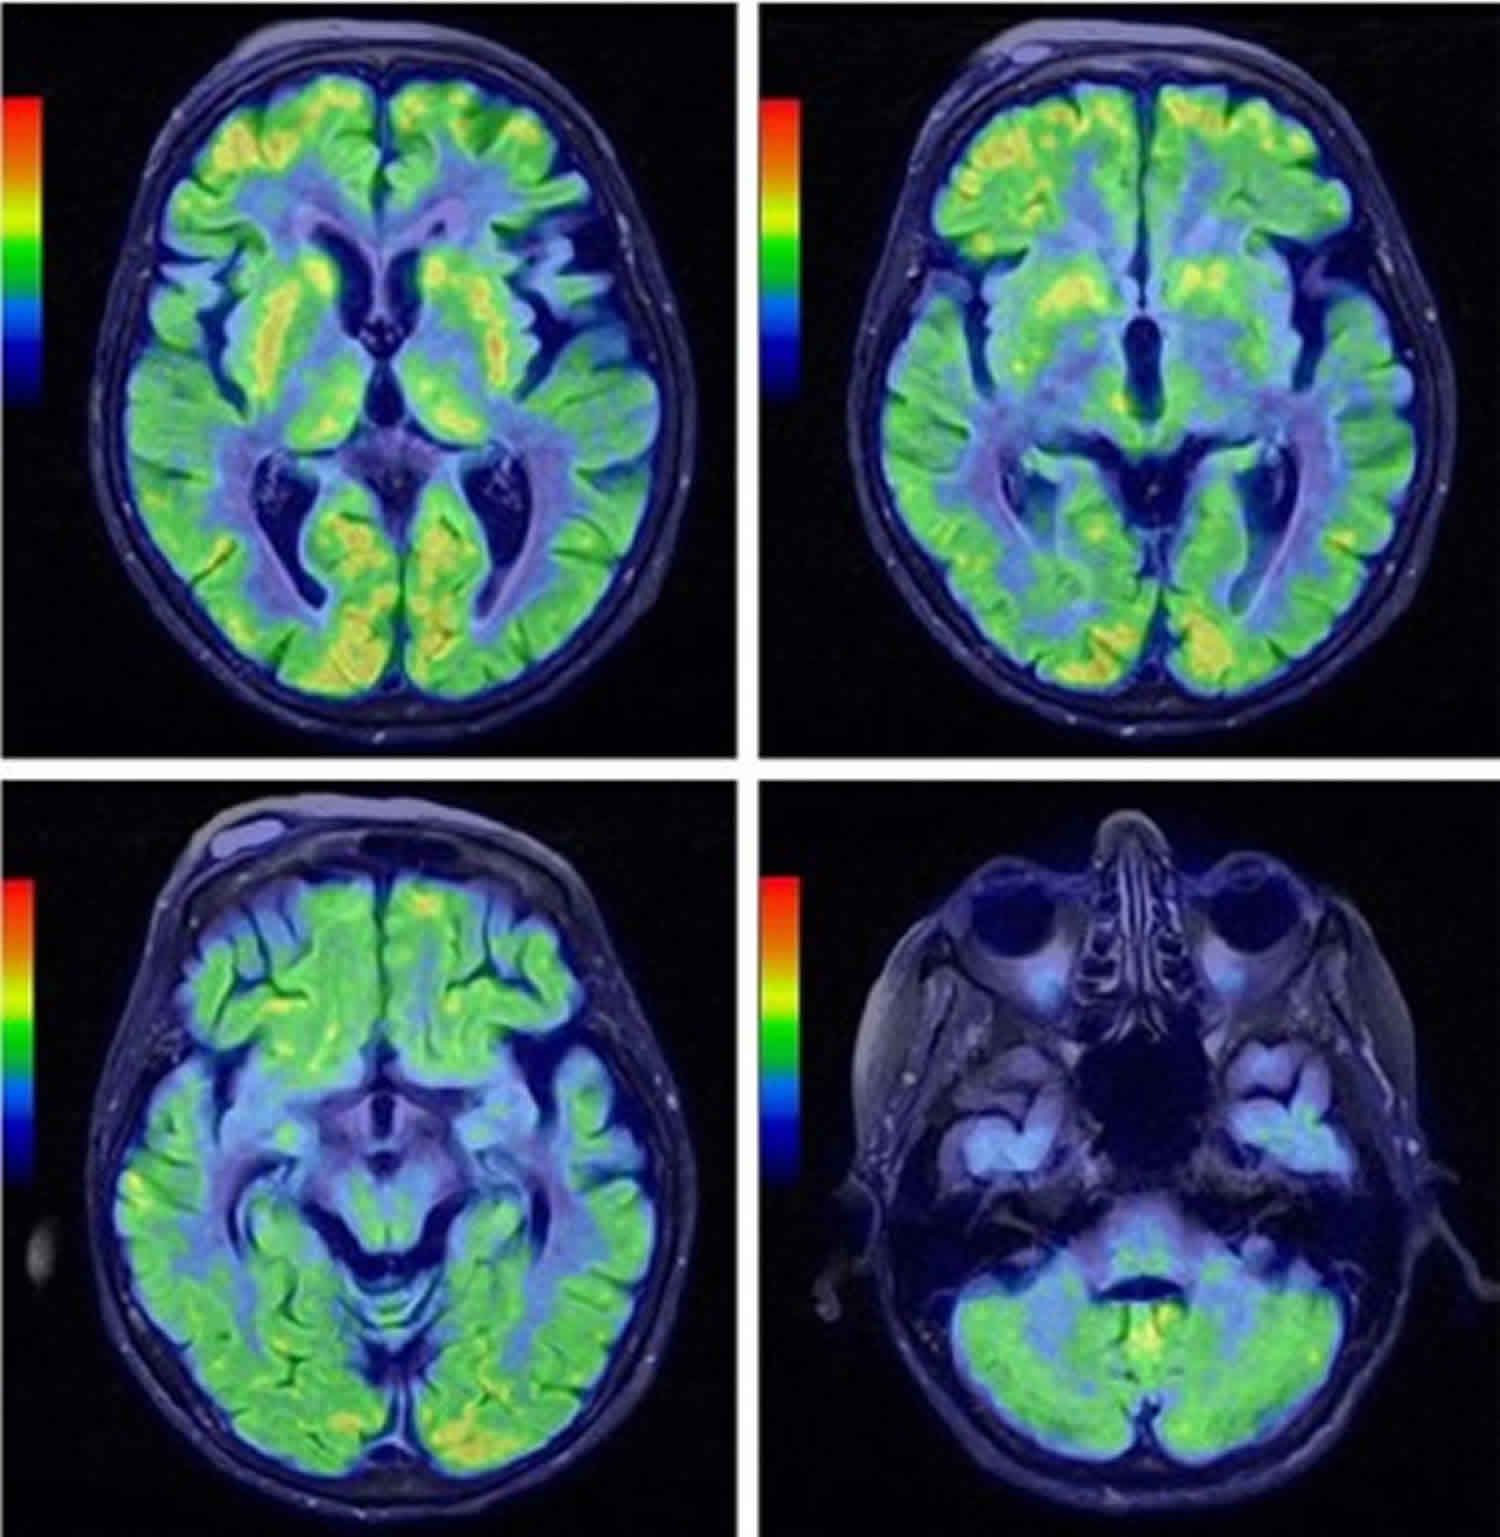

Shy-Drager syndrome is a progressive disorder affecting central and peripheral nervous system. It is characterized by degeneration of autonomic nervous system. In addition, various structures in cerebellum along with vagal nuclei are also degenerated. The condition is usually associated with orthostatic hypotension, impotence, bladder and bowel problems. Tremor, postural instability, and rigidity are also prominent features of Shy-Drager Syndrome. Reference: https://www.sciencedirect.com/topics/neuroscience/shy-drager-syndrome Image via: https://healthjade.net/shy-drager-syndrome/

Can someone tell me what is the name of the investigation presented above and what does the colours represent?

Why there is no sagital or coronal image's and why only diffusion image's are present.